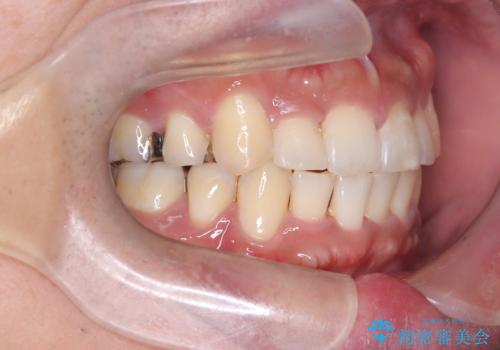

【ワイヤー矯正】八重歯と下の歯の凸凹を治したい

- 主訴:右上の八重歯と、下の歯の凸凹を治したい

上顎右側第一小臼歯と下顎右側第一小臼歯を抜歯しワイヤー矯正を行いました。

右側2級、左側1関係だったため、右側上下第一小臼歯を抜歯し、ワイヤー矯正を行いました。